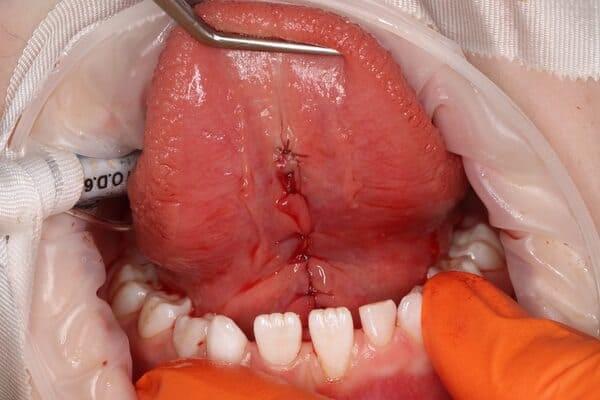

Дівчинка 7 років, перше вересня, гойдалка… Вивих постійного зуба: якщо в такій ситуації зволікати, дитина може втрати постійний зуб назавжди. Батькам порекомендували нас і пацієнти одразу приїхали. Через складність і травматичність процедур вирішено проводити лікування в анестезіологічному супроводі. Зуб поставлений на місце (репонований), проведена хірургічна обробка і ушивання рани губи. Останнє фото через рік після травми: зуб на місці і корінь продовжує розвиватись, губа повністю загоїлась